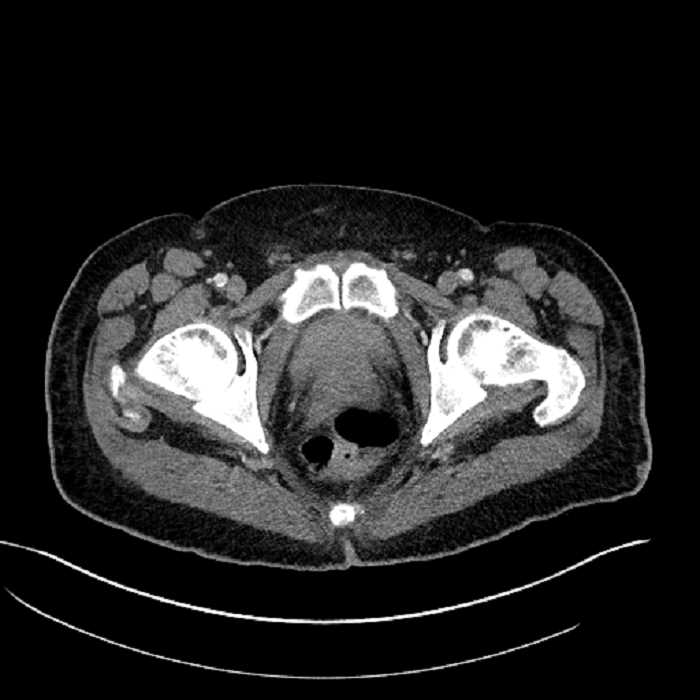

• Mild mural thickening of a segment of the sigmoid colon with adjacent fat stranding and a 1.5 cm fluid and gas collection along the tip of an inflamed diverticulum

• Loss of the normal fat plane between this collection and adjacent loops of small bowel, which demonstrate mural thickening

• High grade stenosis of the left common iliac artery, with the left internal and external iliac arteries remaining patent

Acute sigmoid diverticulitis complicated by a small contained perforation and a large abscess in the right hepatic lobe. Additional small subcapsular abscesses along the anterior margin of the left hepatic lobe.

Additionally, loss of the normal fat plane between the peridiverticular collection and adjacent thickened loops of small bowel raises the potential for an enterocolonic fistula.

High grade stenosis of the left common iliac artery. The left external and internal iliac arteries are patent.

Hepatic abscess showing the double target sign with low density internally surrounded by a thin inner enhancing rim (red arrow) and ill-defined outer low density rim (yellow arrow). Blue arrow indicates an internal septation. Red arrows: additional smaller subcapsular abscesses. Red arrow: focal contained perforation associated with diverticulitis.